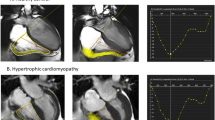

CMR strain analysis was performed to measure global 2D biventricular longitudinal (GLS) and RV radial strain (GRS) using commercially available software (TomTec Imaging Systems Corp, Munich, Germany). This involved employing a semi-automated tissue tracking algorithm to track myocardial deformation throughout the cardiac cycle on standard cine SSFP images. Manual adjustments were made to ensure optimal and appropriate myocardial tracking as required. Peak 2D longitudinal strain was measured from the three standard apical long axis planes and averaged to determine LV GLS. RV peak strain was determined from a horizontal long-axis cine image. Peak RV GLS strain was calculated as the mean peak strain including all segments of the RV free wall and inter-ventricular septum (Fig. 3). Mean peak RV longitudinal free wall strain was defined as the mean peak strain of the three RV free wall segments. RV radial strain was measured in a similar fashion in 6 short axis segments from a mid-ventricular level cine short axis image. The mean peak value for each of the six segments was determined and averaged to calculate RV GRS (Fig. 4).

Right ventricular longitudinal strain cardiac magnetic resonance strain analysis was performed offline using a semi-automated tissue tracking algorithm to track myocardial deformation throughout the cardiac cycle on a horizontal long axis cine image (a) and determine regional and global peak right ventricular 2D longitudinal strain (b, c). From this, mean peak RV free wall was defined as the mean peak longitudinal strain of the three right ventricular free wall segments

Right ventricular radial strain cardiac magnetic resonance strain analysis was performed offline using a semi-automated tissue tracking algorithm to track myocardial deformation throughout the cardiac cycle on a mid-ventricular level cine short axis image (a). The mean peak value for each of the six segments was determined (b, c) and averaged to calculate right ventricular global radial strain